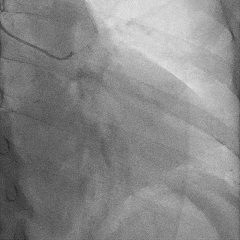

术前冠脉造影:

术前冠脉功能学全面评估:

▶IMR:24;CFR:2.5;FFR:0.76(+)。